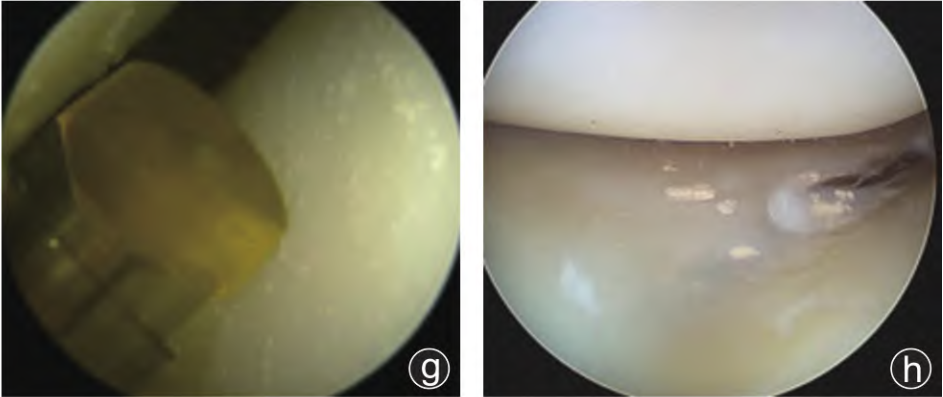

典型病例見(jiàn)圖1。

圖1 病人,男,38歲,因左膝關(guān)節(jié)腫痛、活動(dòng)受限1年,加劇1個(gè)月入院。入院診斷為“左膝關(guān)節(jié)痛風(fēng)性關(guān)節(jié)炎”,WOMAC評(píng)分:53分,Kellgren?Lawrence分級(jí):I級(jí),行左膝關(guān)節(jié)關(guān)節(jié)鏡下高頻脈沖沖洗術(shù)。

置入高頻脈沖沖洗槍(f),沖洗流量設(shè)為500 mL/min,沖洗壓力:5 psi,脈沖頻率1320~1500次/min。

鏡下高頻脈沖沖洗槍清理股骨髁、脛骨平臺(tái)的痛風(fēng)結(jié)晶(g),股骨髁和脛骨平臺(tái)關(guān)節(jié)軟骨(h)與半月板(i)痛風(fēng)石清理滿意且無(wú)軟骨損傷。